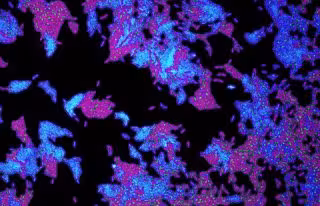

Archivo - Células de la bacteria patógena Pseudomonas aeruginosa utilizada en el estudio

Archivo - Células de la bacteria patógena Pseudomonas aeruginosa utilizada en el estudio - SEAN BOOTH - Archivo